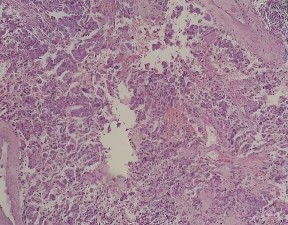

Posteriormente, se realizó un estudio de tomografía abdominal contrastada con resultado de una masa sólida de bordes definidos localizados en el espacio retroperitoneal de la región intercava, inmediatamente anterior al disco intervertebral L2-L3, que medía 26 x 23,9 x 28,8 mm, con realce intenso a la aplicación de sustancia de contraste sugestiva de paraganglioma retroperitoneal (Figura 1 y Figura 2).

Figura 1 Estudio de tomografía computarizada del abdomen: masa sólida de bordes definidos ubicada en el espacio retroperitoneal de la región intercava

Figura 2 Estudio de tomografía computarizada del abdomen: realce intenso a la aplicación de sustancia de contraste sugestiva de paraganglioma retroperitoneal